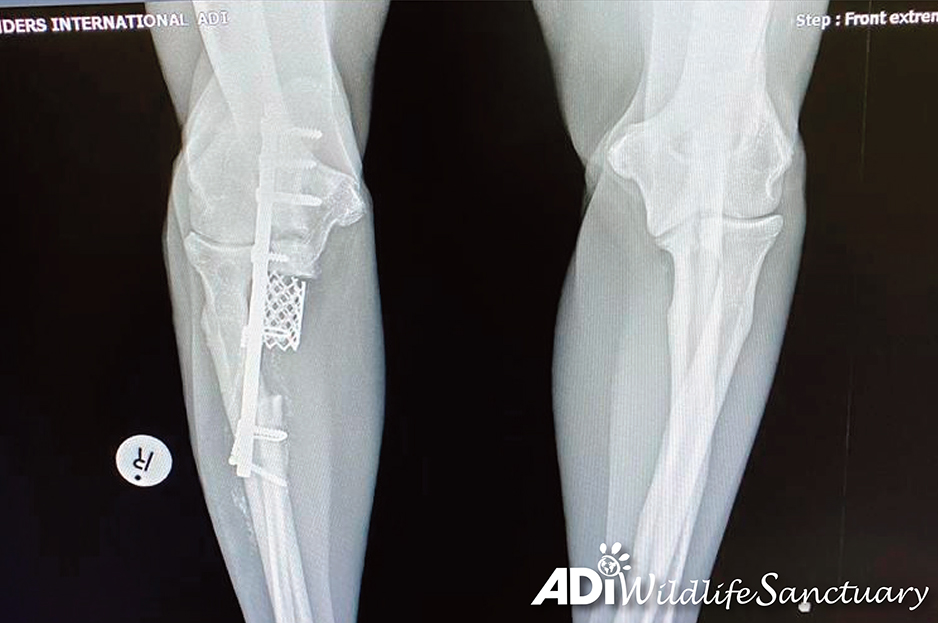

Following Guatemala’s ban on animal circuses, ADI arrived at the circus with officials in 2018 and seized Sasha, taking her to our Temporary Rescue Unit where our veterinary team examined her leg with x-ray, ultrasound, blood samples. The diagnosis was a slow-moving fibrosarcoma, moving up her leg, destroying the bone. We sent the pictures to ADI Wildlife Sanctuary veterinarian Dr Peter Caldwell in South Africa.

We moved our circus survivors from Guatemala to South Africa in January 2020, where Sasha could get the help she needed. Dr Caldwell decided on a radical and ground-breaking approach – to remove all the diseased bone and replace it with a titanium implant.